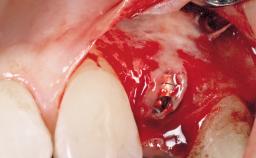

Late Placement of an Implant in a Maxillary Left Central Incisor Site

A 30-year-old female patient had lost tooth 21 and was referred to our clinic for consultation and treatment. Due to advanced apical infection, tooth 21 had been extracted two months earlier at another clinic and an acrylic-resin tooth had been bonded to the adjacent teeth. The patient desired implant treatment to avoid any damage to the adjacent natural teeth. While the patient had no history of any systemic disorder, she was a heavy smoker and exhibited medium to advanced periodontitis in the entire jaw. After the initial treatment to achieve a pocket probing depth of less than 4 mm and no bleeding on probing, a decrease in the height of the papillae mesial and distal to the extraction site and overall gingival recession were observed.

Bone Augmentation Horizontal|Staged

Augmentation Materials Autogenous chips|Membrane